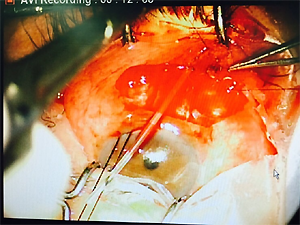

Ahmed valve implant operation

아메드 밸브 삽입 수술

난치성 녹내장의 치료를 위해 안압을 조절할 수 있는 방수유출장치를 삽입하는 수술

녹내장 발생기간이 짧고 눈 구조의 변형이 형성되기 전에 시행할 경우 효과가 큼

8.ahmed implant 를 scleral flap 안으로 insertion 후 nylon 8-0 로 고정